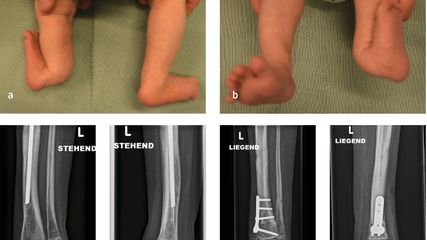

Angeborene Fehlstellungen des Unterschenkels

Kongenitale Deformitäten des Unterschenkels gehören zu den seltenen, aber medizinisch bedeutenden und operativ herausfordernden Diagnosen der Kinderorthopädie. Eine differenzierte ...